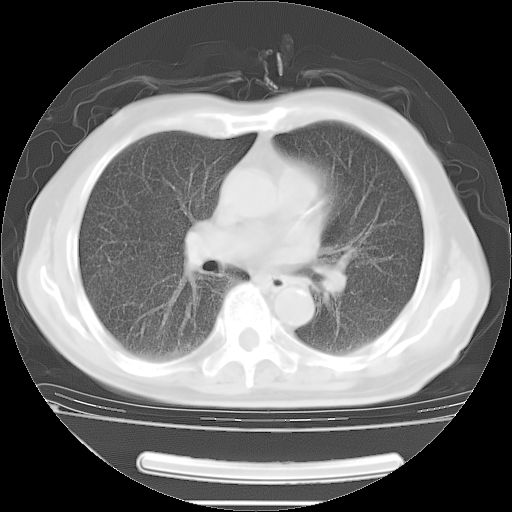

今天复查肺部CT,发现双肺广泛磨玻璃样改变。所以我把3月19日和5月9日相隔50天的肺部CT上传。请大家会诊。

2009年3月19日肺部CT片。

2009年3月19日肺部CT